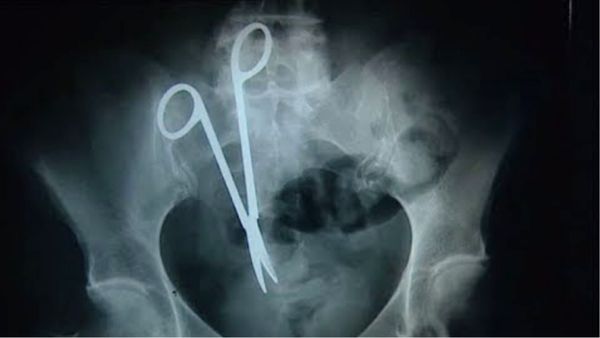

MP में सरकारी डॉक्टरों की लापरवाही! महिला के पेट में छोड़ दी थी कैंची, 10 साल बाद सर्जरी कर निकाली गई

Saturday, August 24, 2024, 19:53 [IST]